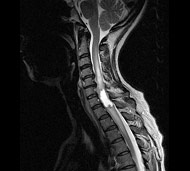

Спинальна магнітно-резонансна томографія (МРТ). Замість радіаційного випромінювання в МРТ використовуються потужні магнітні і радіохвилі для отримання зображення поперечного перерізу хребта. МРТ чітко відображає спинний мозок і нерви і забезпечує краще зображення пухлин кісток, ніж комп'ютерна томографія (КТ). Вам можуть ввести в вену кисті або передпліччя контрастну речовину, яка висвітлює деякі пухлини. Крім цього, використовують сканери з високою інтенсивністю сигналу для виявлення невеликих пухлин, які можна не помітити.